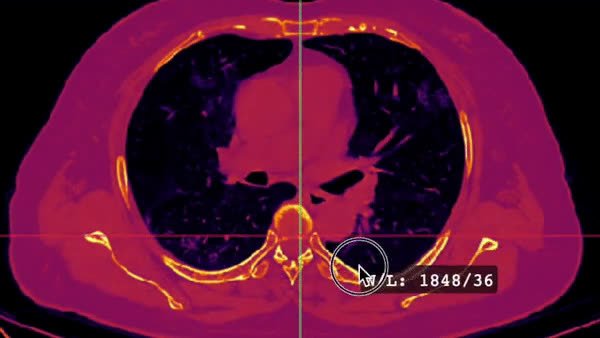

Screenshots

![]() View Video | ![]() View Video |